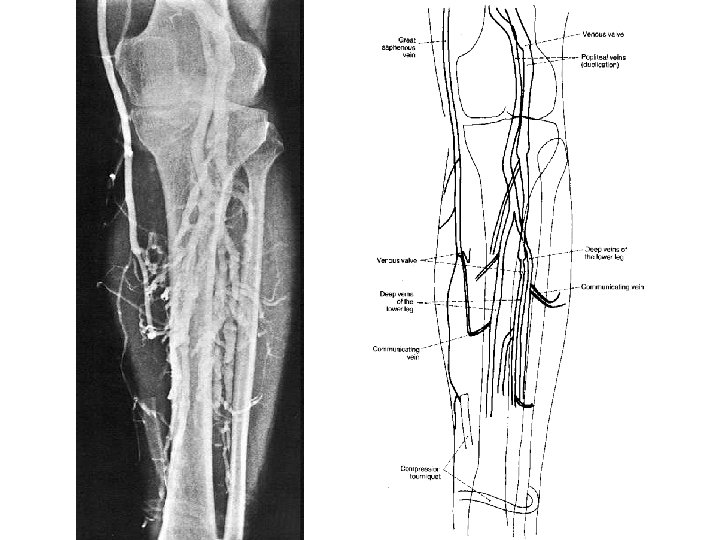

Vv. digitales dorsales – vv. metatarseae dorsales – rete venosum dorsale pedis, rete venosum plantare pedis – vv. intercapitulares v. marginalis med. – v. saphena magna v. marginalis lat. – v. saphena parva (v. femoropoplitea)

femur v. saphena magna

V. SAPHENA MAGNA - v. saphena accessoria - v. epigastrica spf. - v. circumflexa ilium spf. - vv. pudendae ext. vv. perforantes